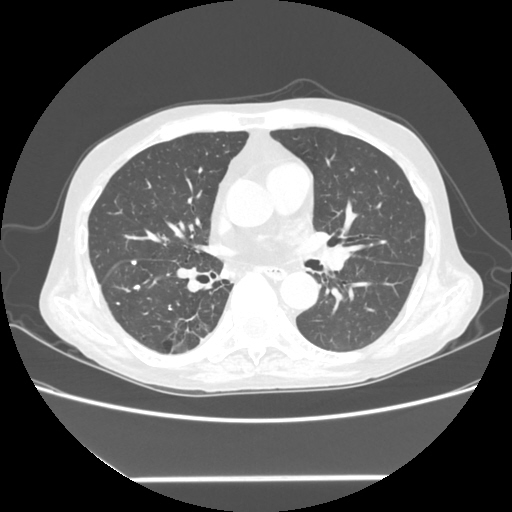

HRCT done on 17Mar16